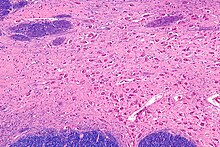

Micrograph of the nucleus basalis (of Meynert), which produces acetylcholine in the CNS. LFB-HE stain.

In the central nervous system, ACh has a variety of effects on plasticity, arousal and reward. ACh has an important role in the enhancement of alertness when we wake up,[13] in sustaining attention [14] and in learning and memory.[15]

Damage to the cholinergic (acetylcholine-producing) system in the brain has been shown to be associated with the memory deficits associated with Alzheimer's disease.[16] ACh has also been shown to promote REM sleep.[17]